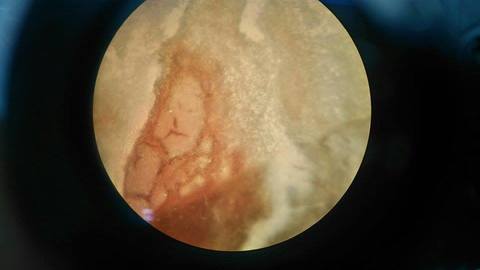

Eritrocitos de la sangre del sapo